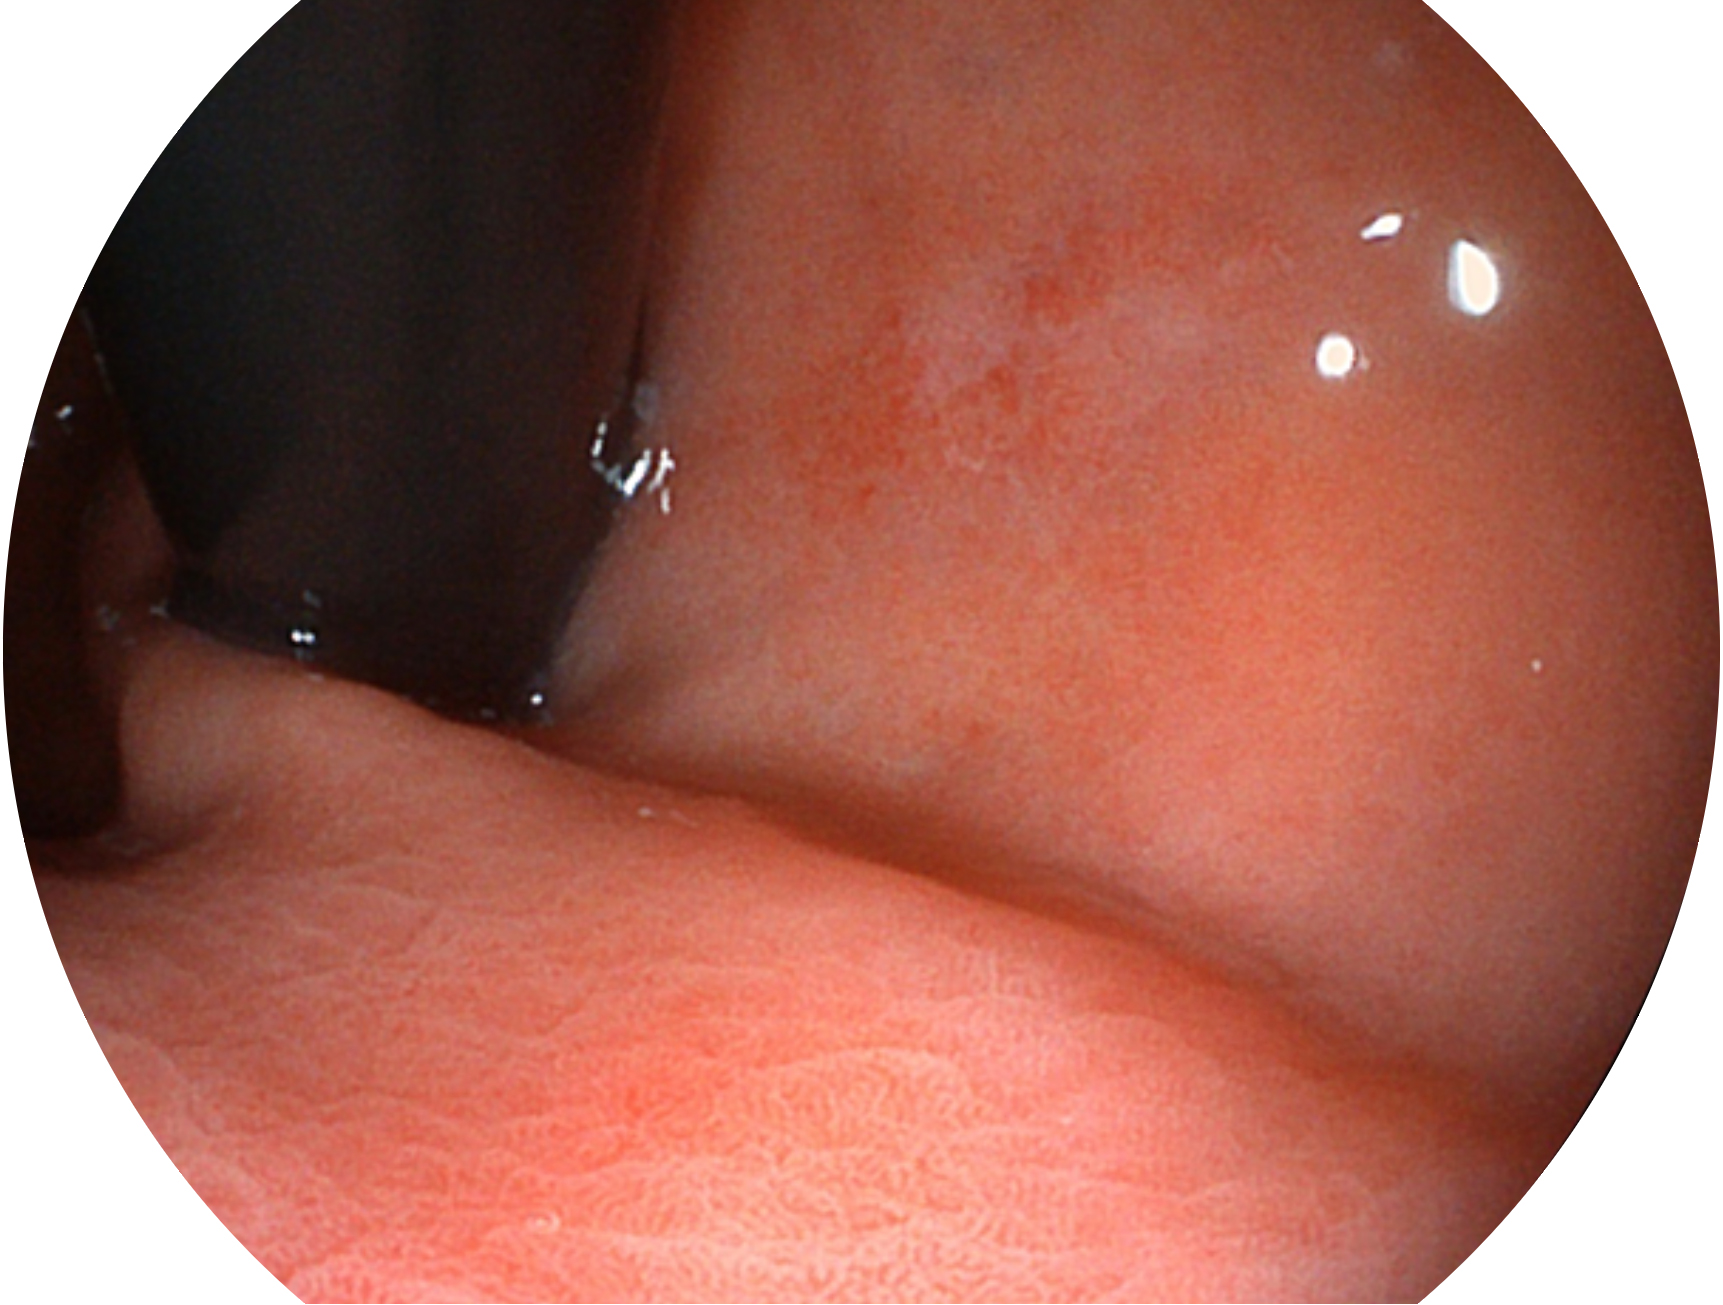

• 白光圖像 SFI圖像